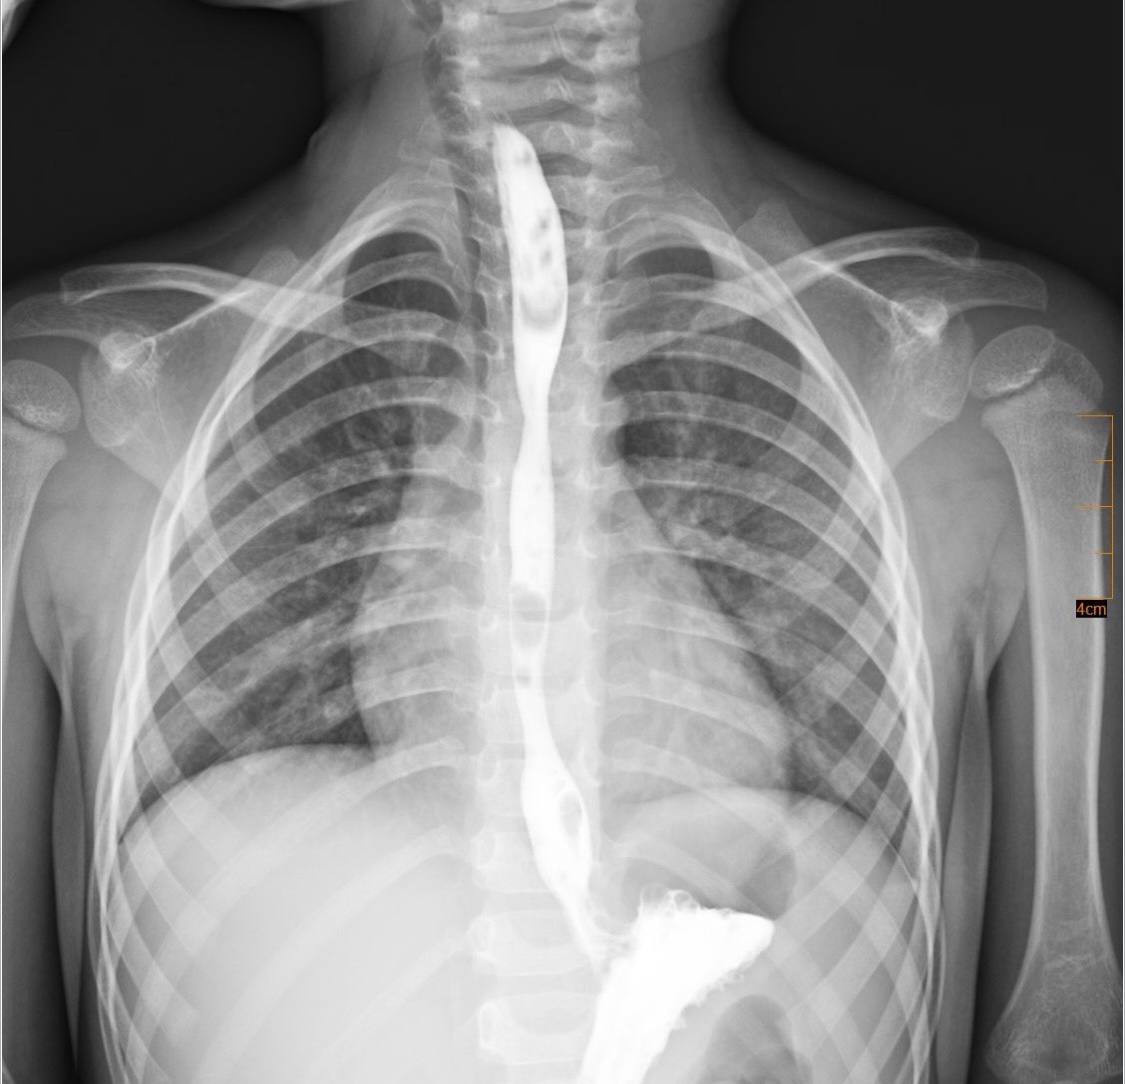

Згодом у хлопчика утворилося критичне звуження стравоходу, що повністю унеможливило прийом їжі через рот. Медики ухвалили рішення провести серію малоінвазивних процедур: звужену ділянку поступово розширювали спеціальним балоном без хірургічних розрізів.

"Це була складна, тривала та поетапна робота, але завдяки злагодженим діям команди нам вдалося уникнути великої травматичної операції", — зазначив керівник Клініки торакальної хірургії та реконструктивної урології Олег Ленів.